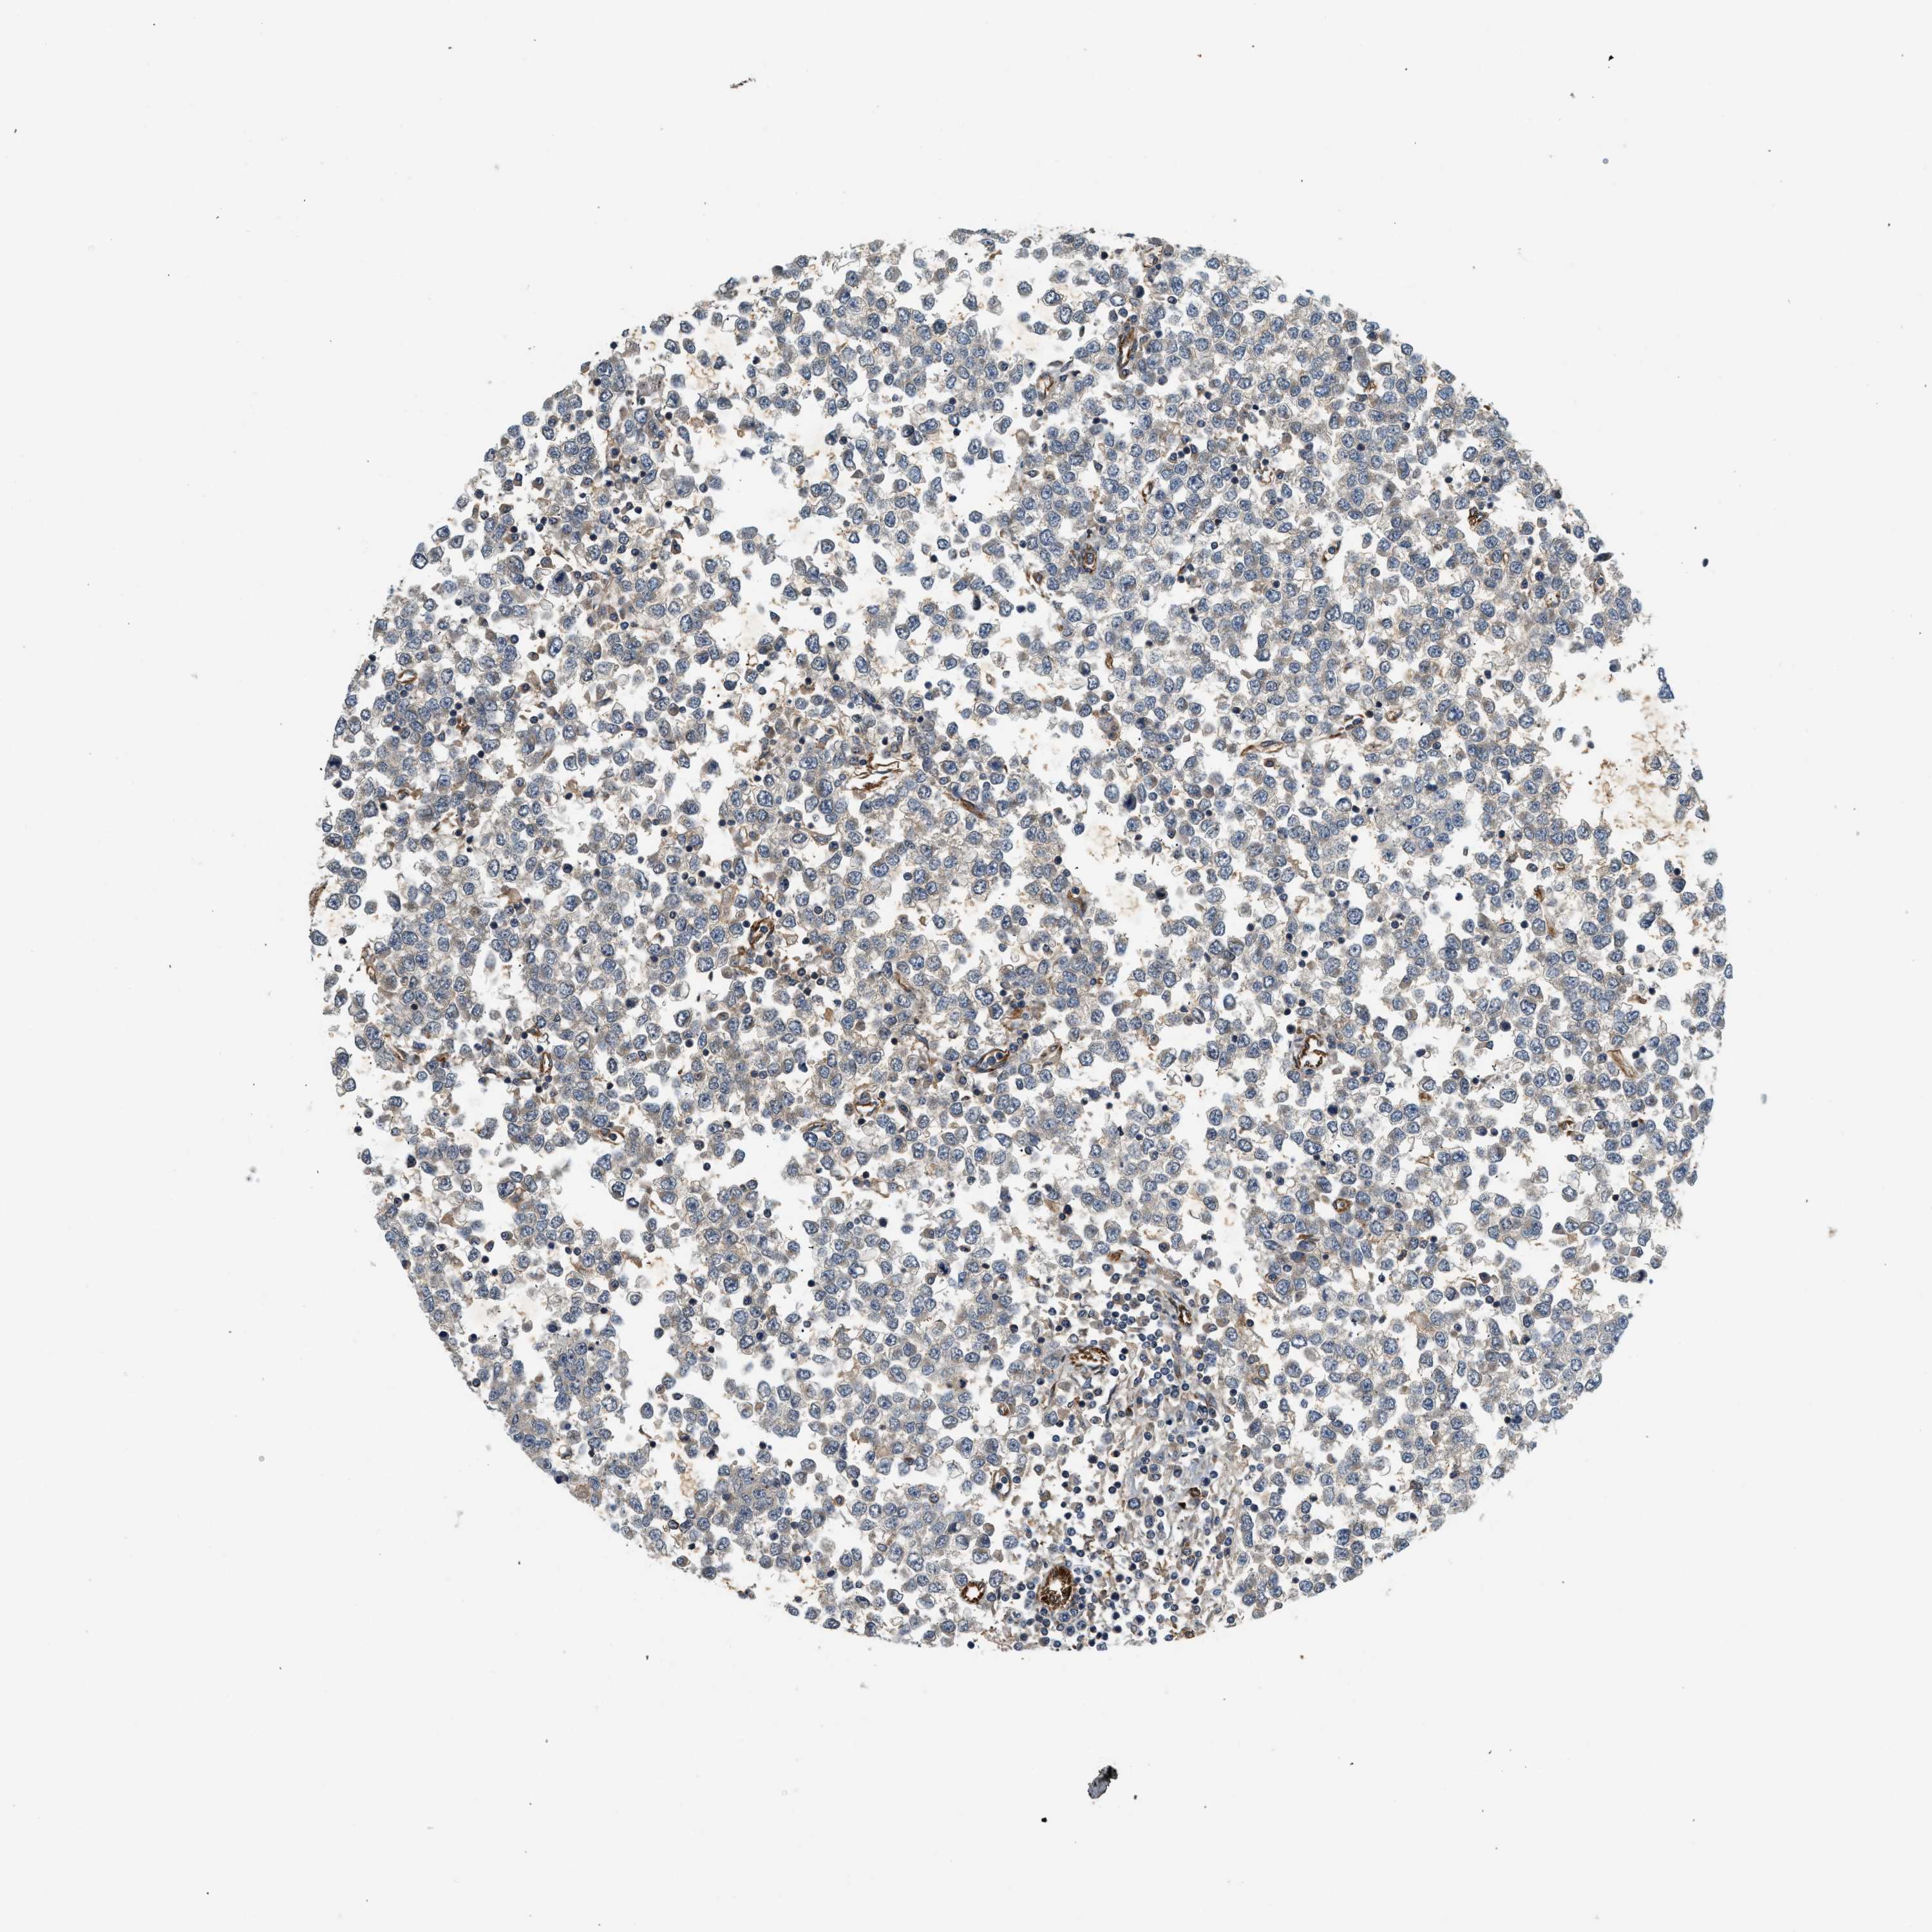

TESTIS CANCER - Protein expressioni

A mouse-over function shows sample information and annotation data. Click on an image to view it in a full screen mode. Samples can be filtered based on level of antibody staining by selecting one or several of the following categories: high, medium, low and not detected. The assay and annotation is described here.

Note that samples used for immunohistochemistry by the Human Protein Atlas do not correspond to samples in the TCGA dataset.

Antibody stainingi

Antibody staining in the annotated cell types in the current human tissue is reported as not detected, low, medium, or high, based on conventional immunohistochemistry profiling in selected tissues. This score is based on the combination of the staining intensity and fraction of stained cells.

Each image is clickable and will lead to virtual microscopy that enables deeper exploration of all samples and also displays staining intensity scores, fraction scores and subcellular localization as well as patient and tissue information for each sample.

Antibody HPA013606

Carcinoma, Embryonal, NOS

Seminoma, NOS